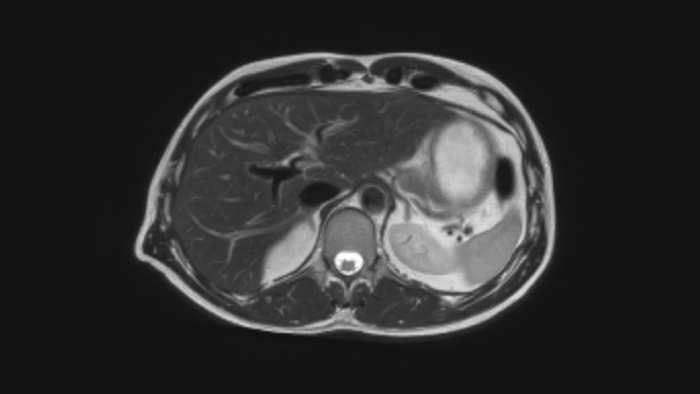

Pewność diagnostyczna Poszerz swoje możliwości obrazowania we wszystkich obszarach klinicznych. Zobacz, jakie korzyści odnoszą inni przedstawiciele Twojej branży.

Sprawdź jak szpital dziecięcy Altona stosuje badania rezonansem magentycznym w pediatrii.